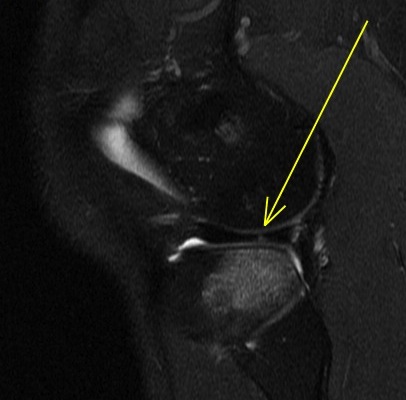

Figure 3 for case Lateral meniscus flap tear and adjacent stress fracture

Figure 3

Knee arthrogram showing lateral meniscus flap tear and adjacent stress fracture.

Lateral meniscus flap tear and adjacent stress fracture